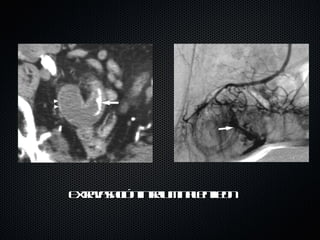

Extravasación intraluminal en ileon

Manejo Angiografía Diagnóstica Terapeutica: Vasoespasmo: Vaspresina, inducido catéter Embolización:  gelfoam , PVA,  microcoils

Manejo Angiografía Descrita por primera vez en 1974 como procedimiento diagnóstico y terapéutico en HDB utilizando coágulos autólogos. Útil en sangrado > 0.5 ml/min Sensibilidad 27  –  77%. Especificidad 98% Complicaciones hasta 10%: sitio punción, RAM contraste Primera opción en sangrado masivo; considerar en sangrado persistente o recidivante. Si se detecta sangrado activo: embolizacion supraselectiva con microcatéter es la eleccion. También puede servir para marcar al cirujano el sitio de sangrado con azul de metileno